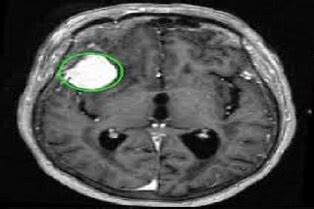

Warthin Tumor Case

Warthin Tumor MRI